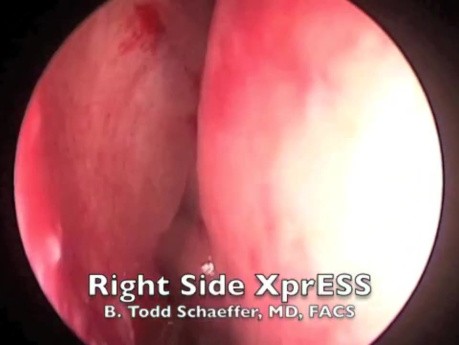

Plastyka balonowa zatoki klinowej

Wideo przedstawia nowoczesną metodę redukcji krwawienia operacyjnego - wykorzystanie balonowej plastyki zatoki klinowej zamiast tradycyjnego zabiegu.

Poszerzanie balonowe otworu zatoki w przebiegu...

Film przedstawia zabieg wykonywany w gabinecie lekarskim - poszerzanie otworu zatoki. Jest to nowa, innowacyjna metoda leczenia przewlekłego zapalenia zatok.

B. Todd Schaeffer

lek.